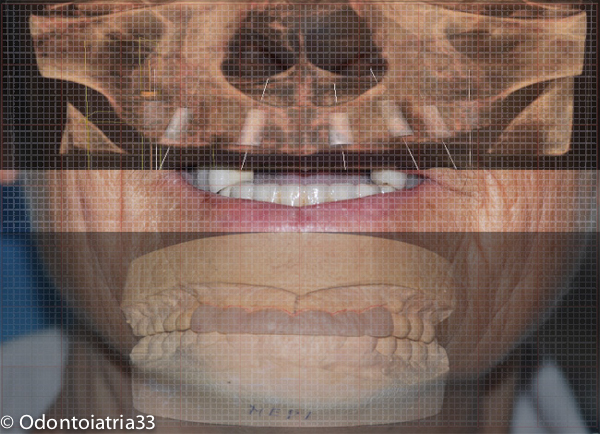

Valutato il quadro clinico e radiografico abbiamo ritenuto il caso di trattare la paziente (che non voleva rimettere mano alle riabilitazioni posteriori e inferiori eseguite presso un altro studio poco addietro), con una chirurgia preprotesica di rimodellamento osseo,contestualmente all'inserimento degli impianti, mediante frese carotatrici, che ci consentissero di prelevare osso prezioso da posizionare eventualmente nelle aree deficitarie, e frese rotanti a rosetta in tungsteno per rifinire i bordi; il tutto sotto abbondante irrigazione di fisiologica sterile al fine di scongiurare un surriscaldamento eccessivo della struttura ossea e quindi un suo critico e non prevedibile riassorbimento. Sono stati fatti scarichi di rilascio laterali molto corti, l'incisione è stata di tipo crestale lievemente palatale al fine di mantenere il massimo della vascolarizzazione e struttura gengivale aderente. La paziente viene trattata nel post-operatorio con terapia antibiotica iniziata dalla sera prima dell'intervento ( 1gr di amoxicillina e acido clavulanico ogni 12 ore per 6 giorni) con sciacqui con chlorexidina digluconato 0,12% 3 volte al dì per 10 giorni, Arnica Montana in compresse sublinguali 5cps 3 volte al dì da tre giorni prima a tre giorni dopo l'intervento.

Trattandosi di guidare al contrario la morfologia ossea tramite rimodellamento abbiamo cercato di trovare un equilibrio fra necessaria riduzione ossea in senso volumetrico antero-posteriore /cranio-caudale e perdita di supporto sul labbro superiore con appiattimento del profilo, posizionando gli impianti un po' più vestibolarizzati e profondi,nonchè lavorando sui profili gengivali mediante provvisori a condizionamento tissutale.

Considerazioni cliniche: in tempi dove la chirurgia implantare computer guidata (CAD /CAM) ci offre un valido aiuto nella gestione di casi più complessi risulta prioritario impiegare tale metodica laddove sia indicata e possibile; la variabile discriminante che ne limita la possibilità di utilizzo risulta però ancora essere la necessità di modificare volumetricamente la morfologia ossea, sia in senso rigenerativo che riduttivo come in questo caso dove ancora la tecnica tradizionale protesicamente guidata e ben programmata può darci buone risorse.